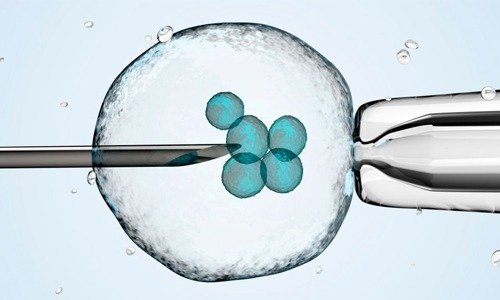

Bone Marrow Transplant

This procedure is used to treat blood-related disorders such as leukemia, lymphoma, and other immune system diseases.